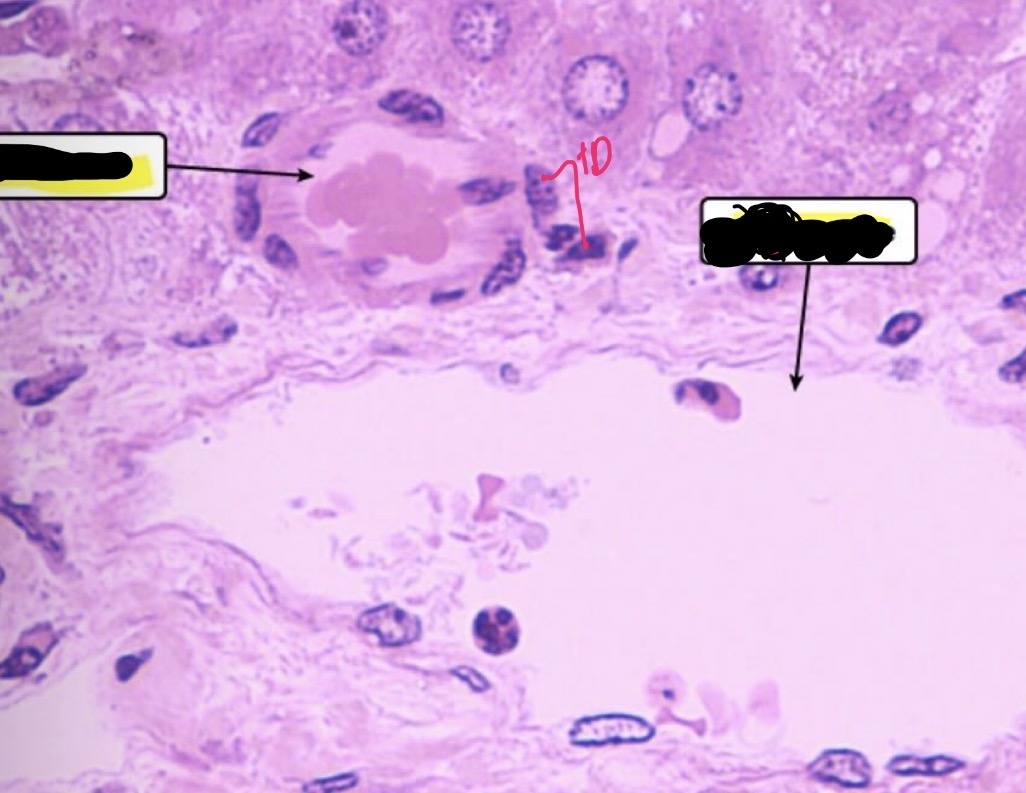

Hepatocytes

Portal Triad

Hepatic Venule

Hepatic Artery

Bile Duct

Liver